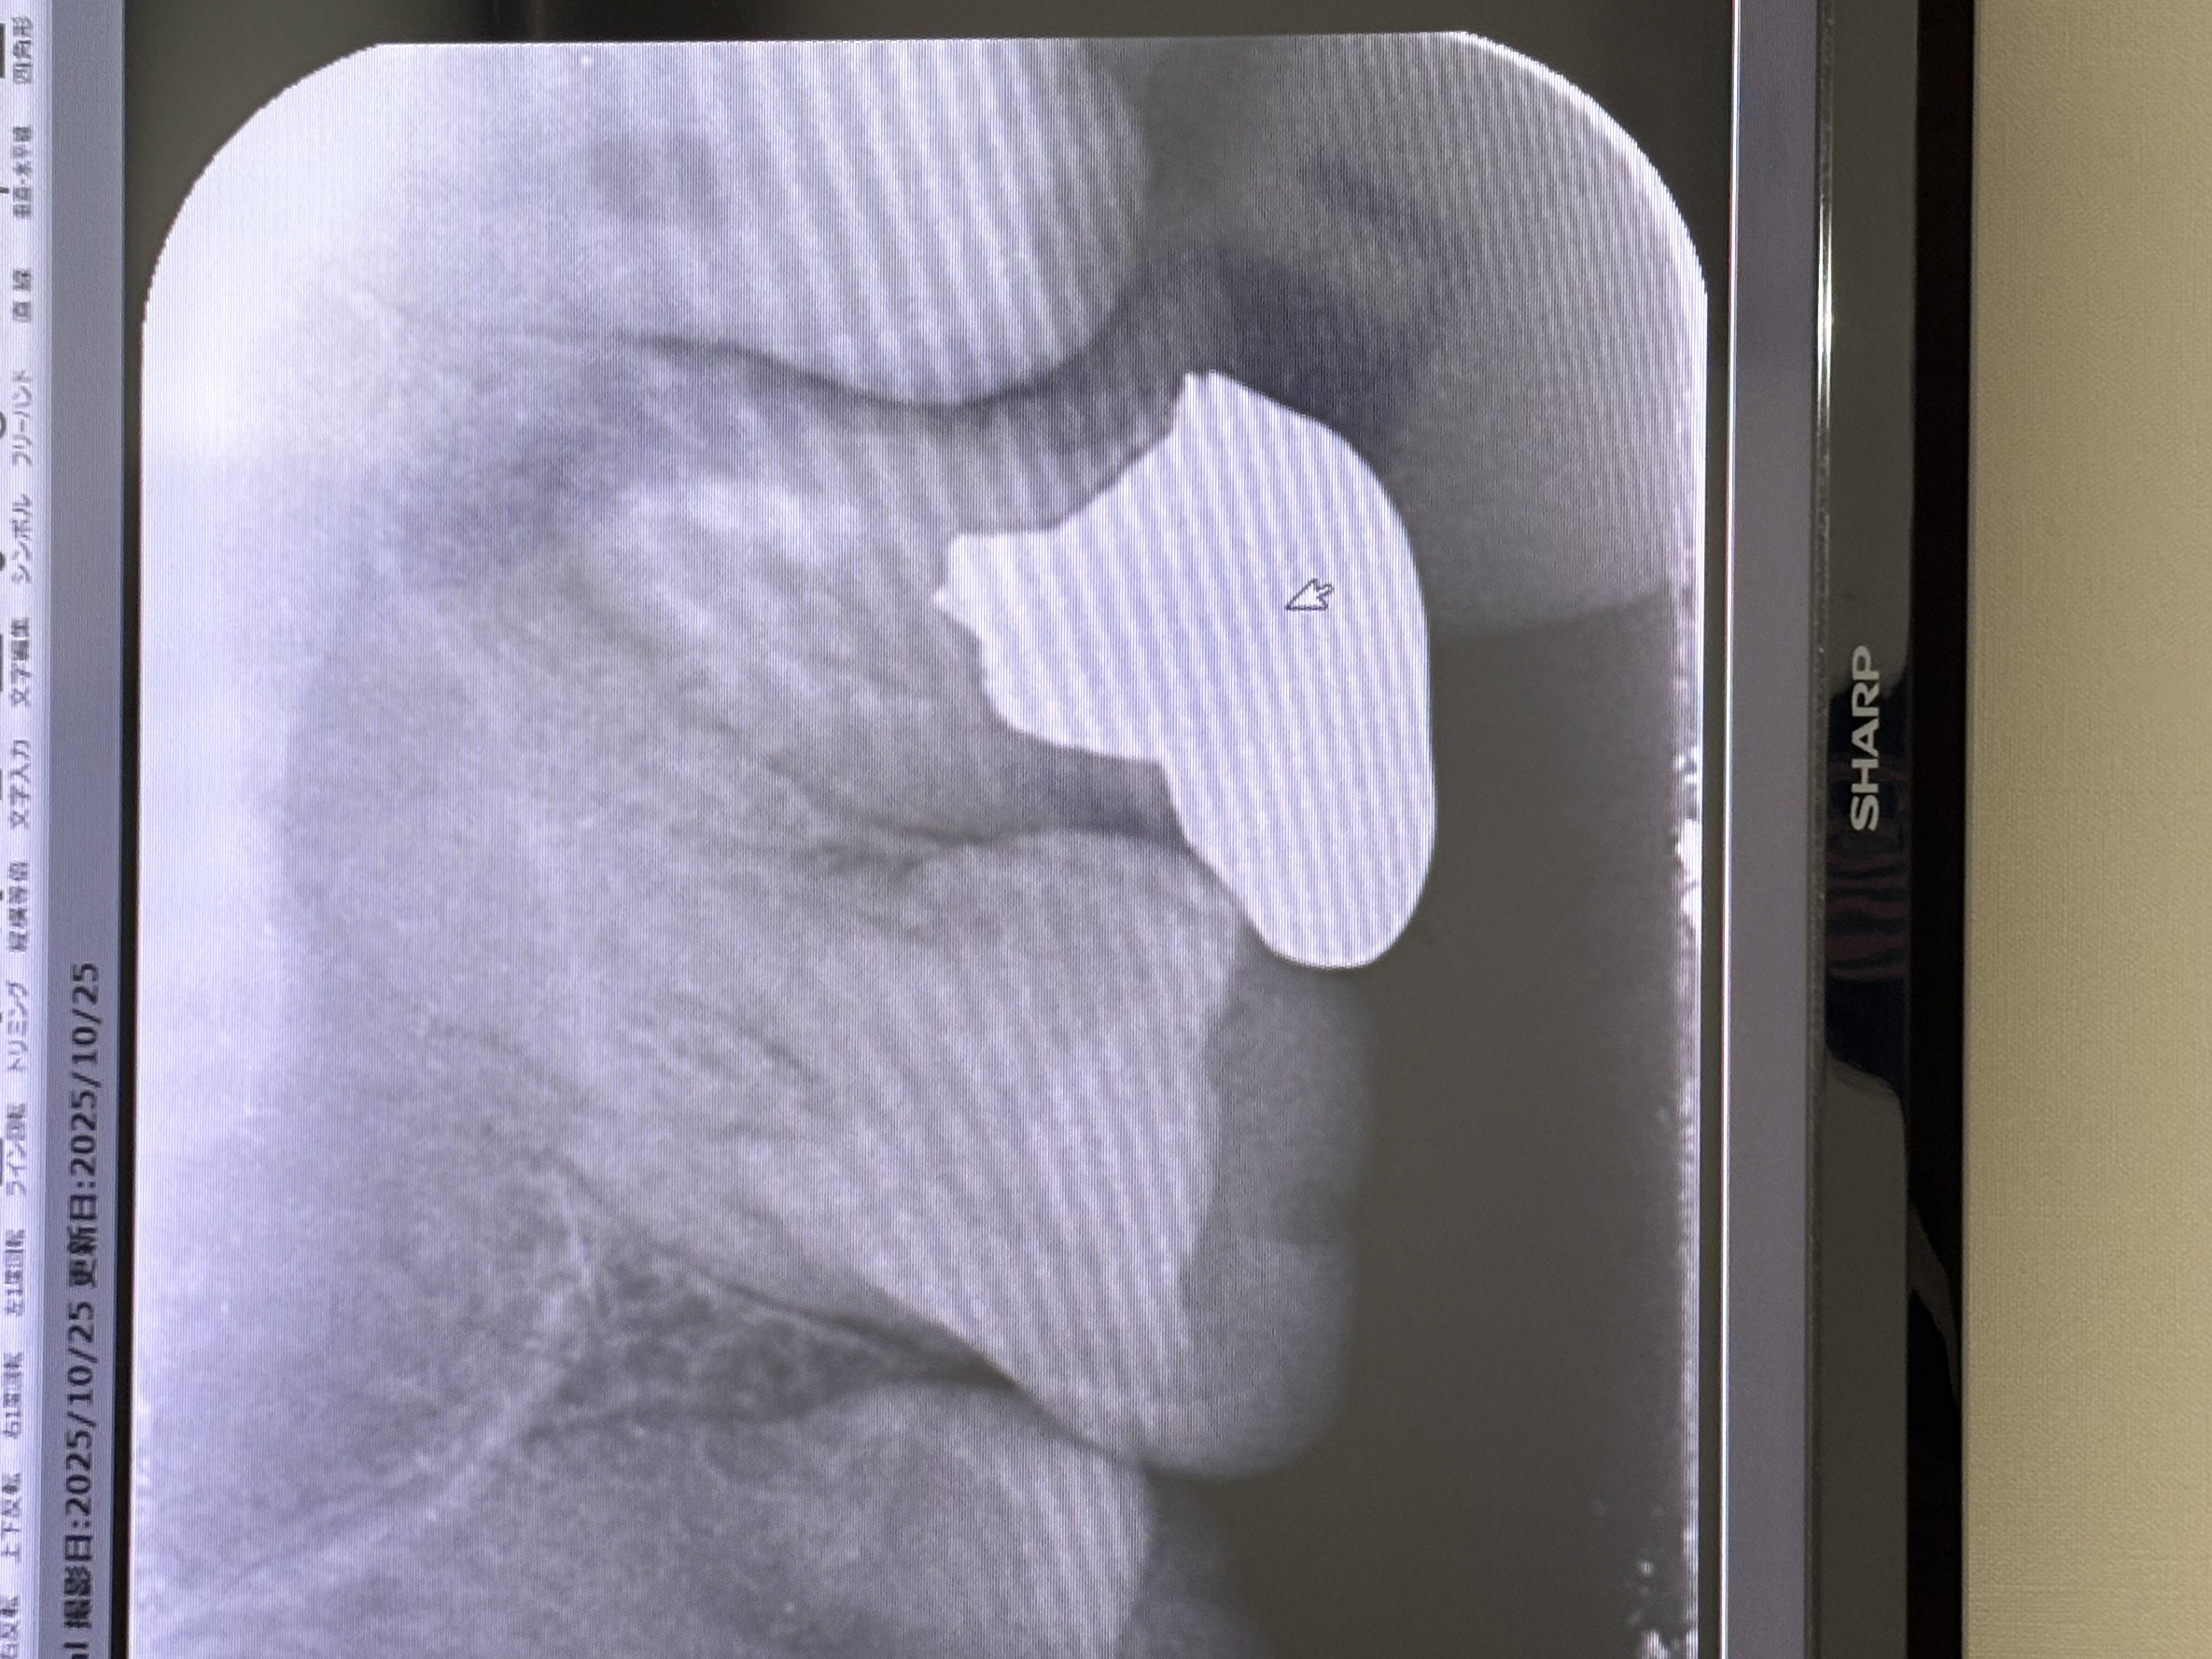

歯性上顎洞炎になっていると言われました。根管治療で歯を残せますか?